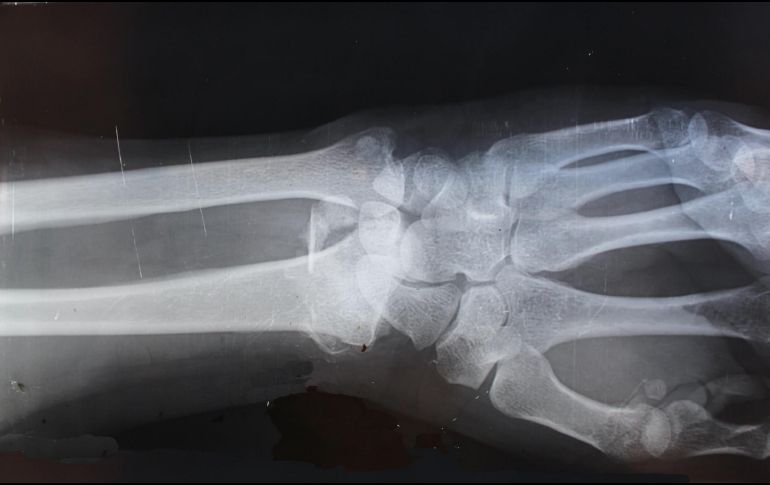

La osteoporosis es una enfermedad en la que la disminución de la masa ósea hace que nuestros huesos se vuelvan frágiles y más propensos a fracturarse.

Aunque las fracturas pueden ocurrir en cualquier parte del esqueleto, suelen ser más frecuentes en las vértebras, fémur,  muñecas y cadera.